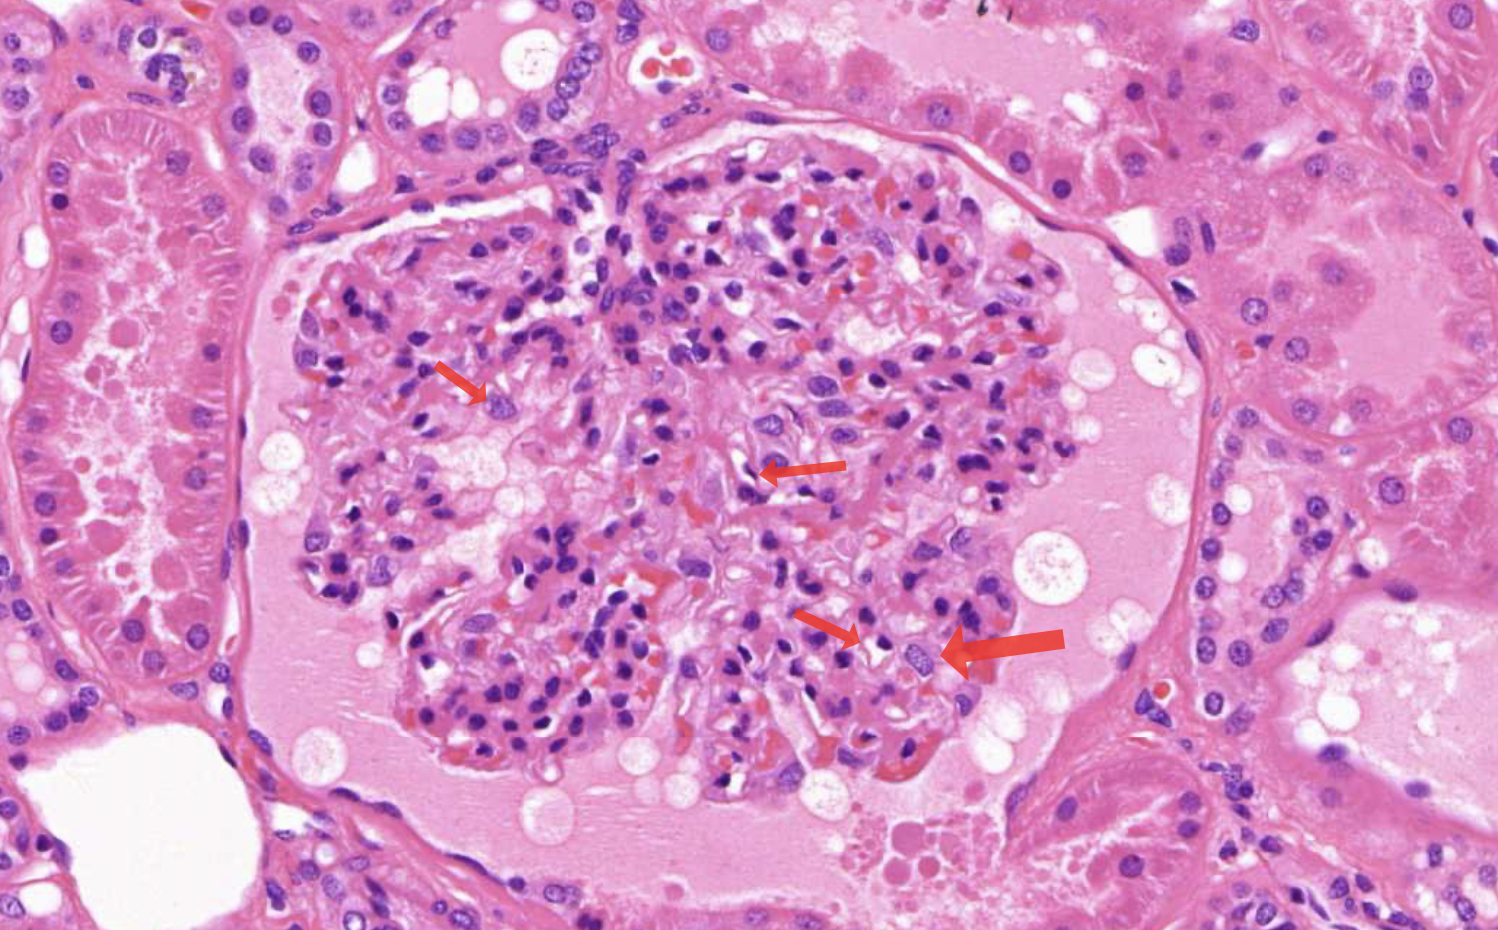

term image

• bowmans space - urinary space

• simple squamous epithelium

• bowmans capsule/glomerulus

• fenestrated capillaries - fenestratins are pores that allow larger molecules to pass through the capillary wall

• endothelial cells - 1st stage of filtration of blood to primary urine

• besement membrane - 2nd

• podocytes - 3rd stage

• mesangial cells - provide structural support (dark irregular nuclei, surrounded by deep pink material)

• vascular pole

• affarent and effeent arteriole

• juxtaglomerular apparatus

• macula densa - regulate blood pressure and filtration rate

• juxtaglomerular cells - secrete enzymes renin

• urinary pole - proximal tubuli